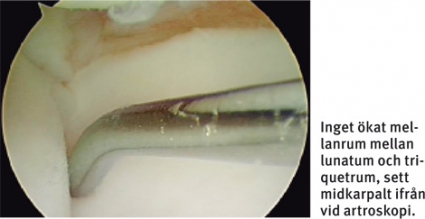

Artroskopi är etablerad standardmetod i diagnostiken. Den ger en direkt uppfattning om graden av instabilitet, vilket MR inte kan ge. Artroskopi ska ske genom portaler i både radiokarpal- och midkarpallederna [9]. Vid artroskopin görs – förutom inspektion – palpation och provokation med hjälp av artroskopihake. Instabilitet i lederna kan då graderas från midkarpala vyn. Vanligaste klassifikation som underlag för val av behandling är Geisslers.

Stabilitetstest i röntgengenomlysning, direkt preoperativt, kan också vara av värde. TFCC-skada är framför allt en klinisk diagnos, där artroskopi mer används för att bedöma skadans utbredning och värdera förutsättningarna för reparation av ligamenten. Differentialdiagnostiskt har artroskopin här dock stort värde för att se andra eventuella ligamentskador och samtidiga broskskador.